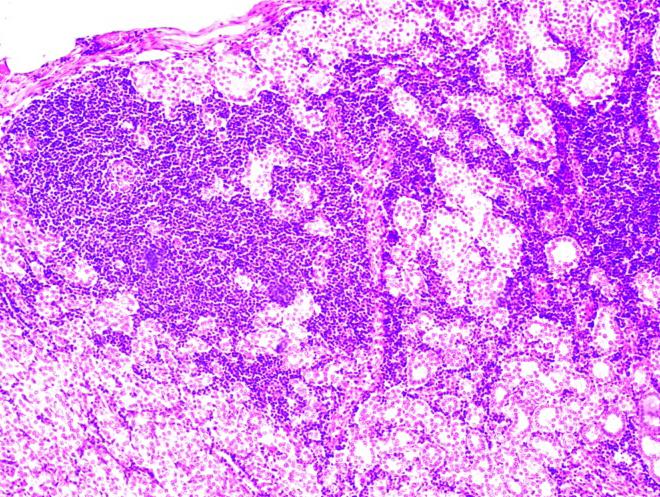

Pseudochistul de pancreas la copii

Dr. Alma Raluca Clinciu, Șef Lucr. Dr. Elena Hanganu, Șef Lucr. Dr. Valentin Munteanu, Dr. Dana Măndrășescu